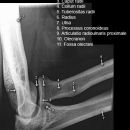

Radiusköpfchen; Greenspan

Beurteilungskriterien